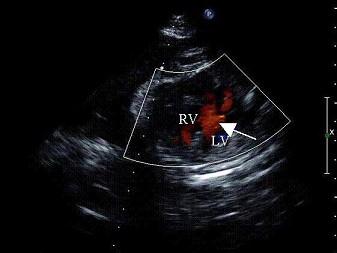

孕8周时感冒,产前超声检查胎儿心脏见图,最可能的诊断是?(?)A.单心室B.房间隔缺损C.室间隔缺损D.大动脉转位E.正常心脏

问题 孕8周时感冒,产前超声检查胎儿心脏见图,最可能的诊断是?(?)

选项 A.单心室 B.房间隔缺损 C.室间隔缺损 D.大动脉转位 E.正常心脏

答案 C